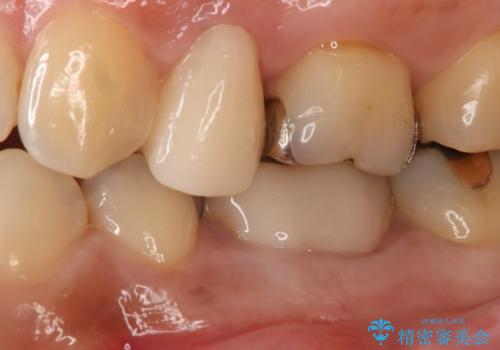

- 左下5番の銀歯をセラミックにやり変え希望の患者様です。

切削量を考慮し、セラミックインレーでの治療を選択しました。

銀歯直下のう蝕を除去しCRで裏層を行った上で、形成・印象を行っています。